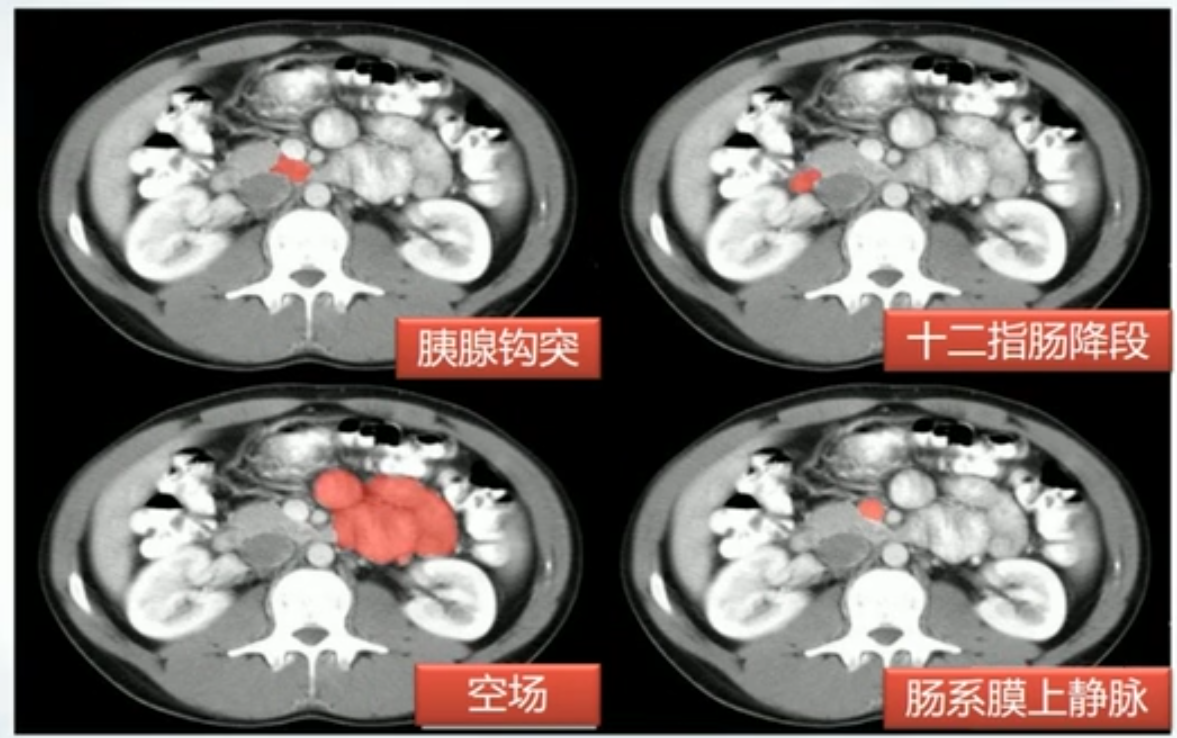

- 十二指肠上段

- 十二指肠后段

- 胰腺段:胰腺后方

- 十二指肠壁段:穿入十二指肠内

肝胰壶腹:胆总管十二指肠内开口和胰管汇合形成,周围有Ossid括约肌,控制胆汁和胰液流出,并防止十二指肠内容物反流

肝CT

- 40~60HU,高于胰,脾

- 肝内管道系统(胆管,肝动脉静脉和门静脉)低于实质,周围小分支多不显示。大血管呈低密度树状影

正常肝重要结构